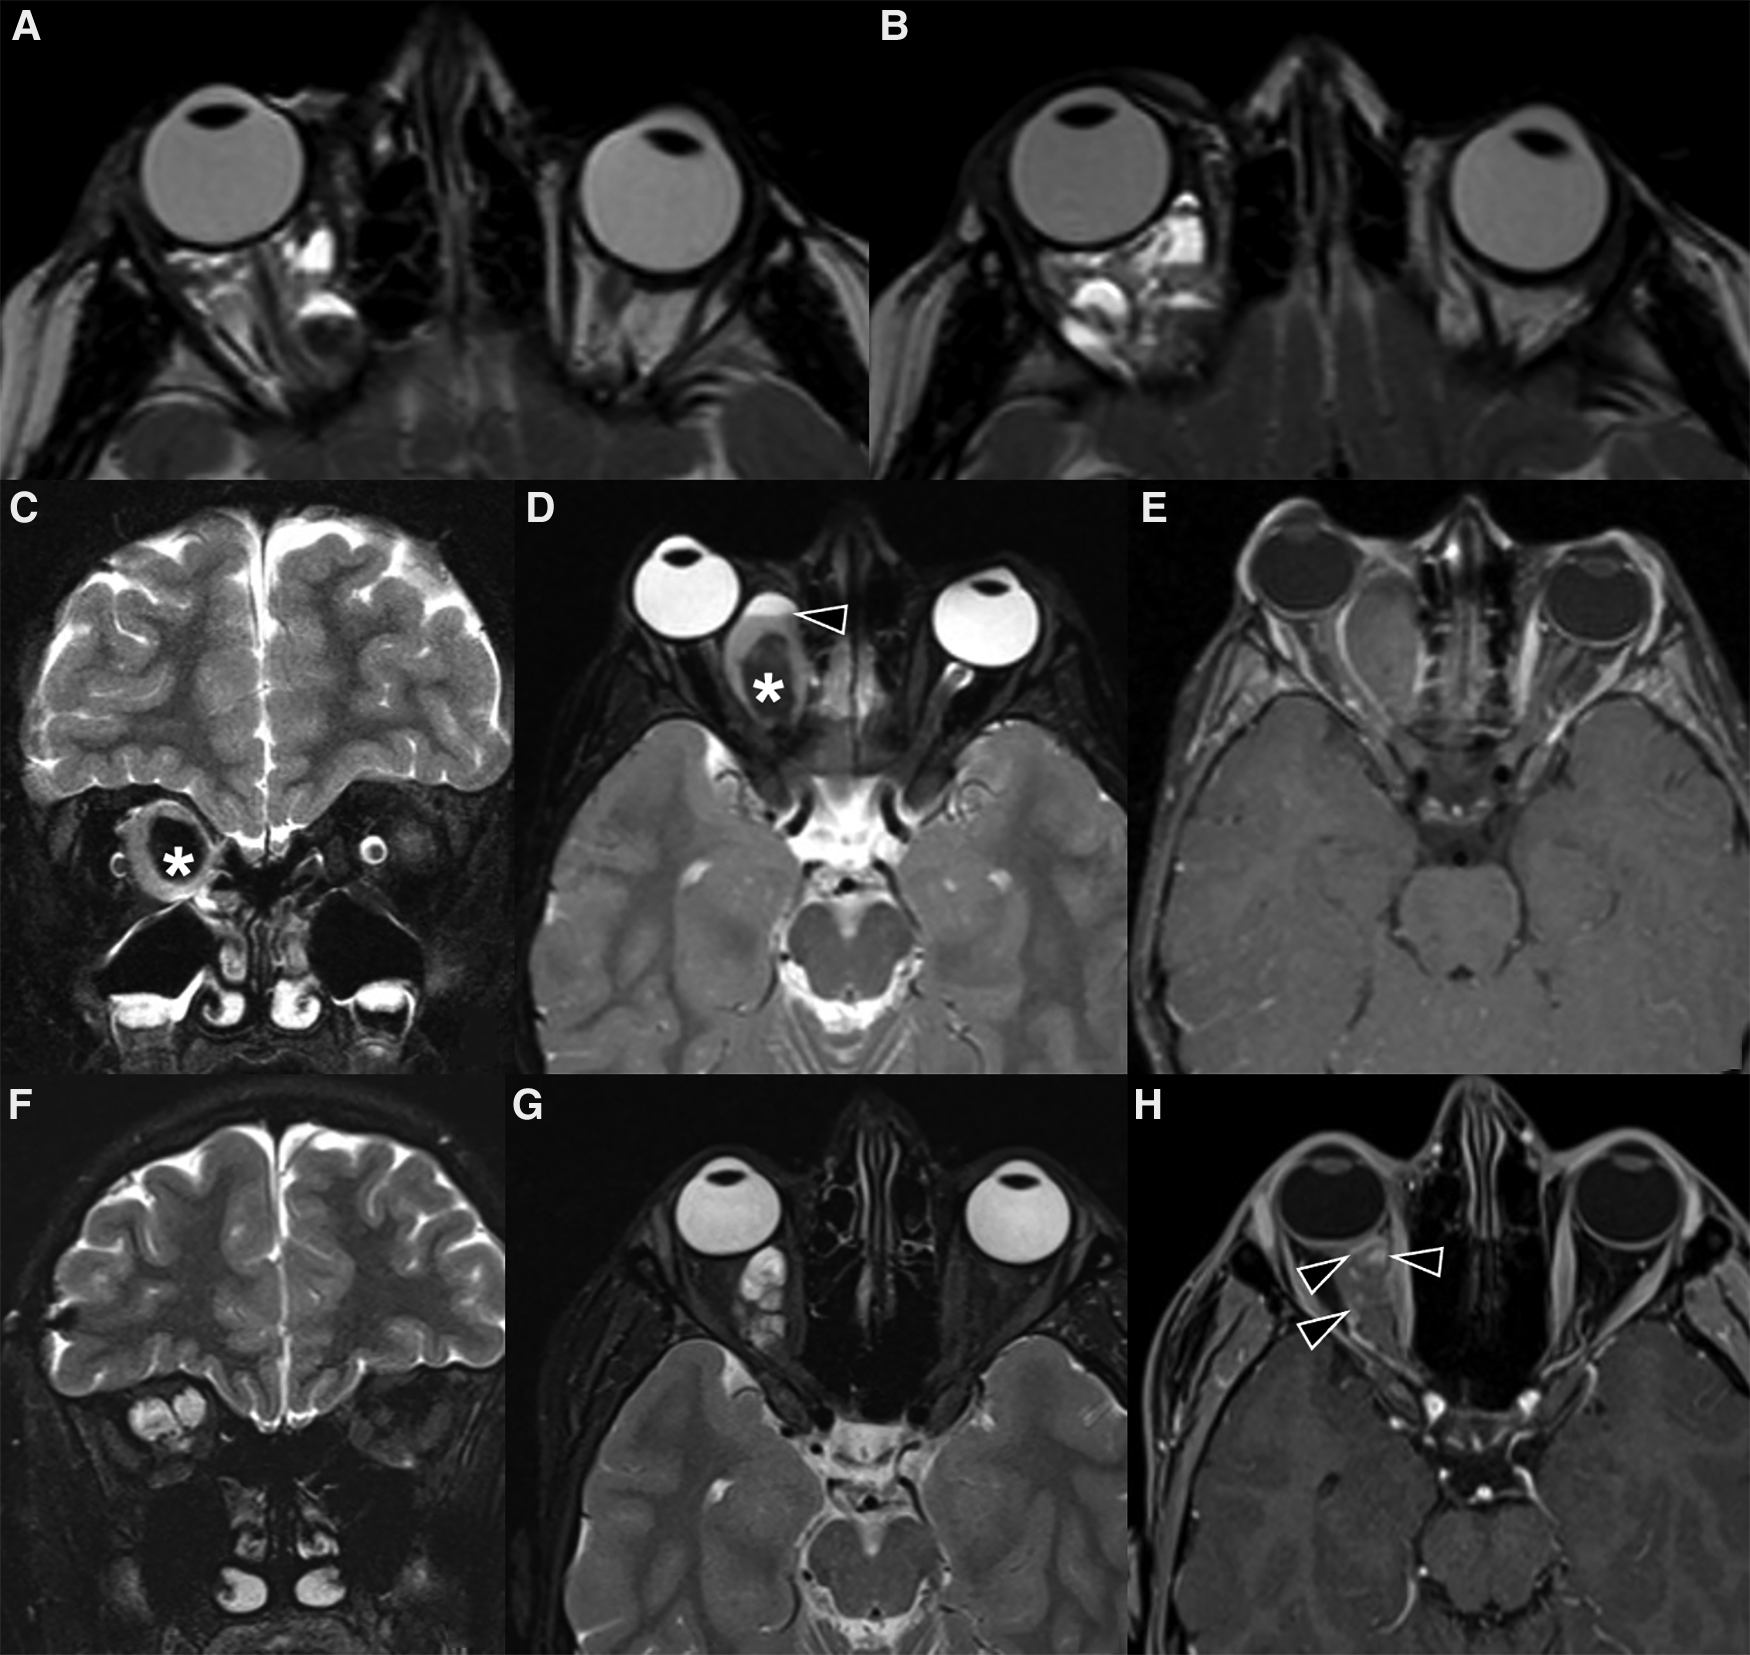

On gray-scale US, LMs appear as ill-defined and mostly anechoic lesions; echogenicity can be more heterogenous in the setting of recent bleeding or infection, even with the formation of possible fluid-fluid levels. The macrocystic lymphatic malformations appear as lesions containing numerous cystic formations of variable dimensions with liquid content separated by thin hyperechogenic septa (64); the lesion is deformable, and compression with the probe alters the shape of the cysts that never collapse completely (65). The microcystic types most often appear as solid hyperechoic formations. At Doppler US, presence of vascular signal is uncommon, as they are slow flow lesions (53) however in some cases it is possible to identify arterial vessels with high resistance confined in the larger septa (64). Owing to their non-encapsulated nature, they tend to violate fascial planes showing a trans-spatial growth pattern, often involving more than one anatomical compartment and being locally aggressive, engulfing and encasing vital structures: for this reason, the use of MR or CT is mandatory to assess the complete extension of the lesion, where MR is most preferable. LMs are usually seen on CT and MRI as poorly circumscribed, lobulated, trans-spatial lesions made up of numerous cystic spaces with intervening septations (Figure 10). The T1 and T2 signal intensity of the lesion depends on the presence and the temporal evolution of blood products: the cystic components are usually iso to slightly hyperintense on T1w imaging and very hyperintense on T2w imaging, with internal septations showing low signal intensity on T2; fluid-blood levels or blood-blood levels can be seen (Figure 10), usually indicating recent intralesional bleeding. After contrast administration, a subtle enhancement of the periphery and the septations may be demonstrated (Figure 10). On the other hand, in LM complicated by infection walls can become visibly thickened and show contrast enhancement (66).

Figure 10. Imaging of lymphatic malformations. (A,B) MRI of a 11-year-old boy with subacute disturbances in visual motility and subtle ptoptosis of the right eye. Axial T2 weighted images show a right intraorbital multiloculated, polylobate and poorly defined mass with fluid-fluid levels, which extends into the extra and intra-conal compartments. The findings were virtually pathognomonic of a lymphatic malformation. (C–H) MRI of a 6-year-old girl with acute right orbital swelling and proptosis. (C–E) Coronal STIR (C) and axial T2 weighted images (D) show a multicompartmental expansile mass with marked compression on the optic nerve and proptosis; the lesion also demonstrates a central marked hypointensity (asterisk in C,D) with no evidence of enhancement on axial post-contrast fat-sat T1 (E). The mass was partially removed surgically, and histology revealed veno-lymphatic malformation. (F-H) 10-year follow-up MR images show how the mass has markedly reduced in size. The multiloculated architecture is more apparent (F,G), with thin intervening septa and blood-fluid levels; on post-contrast T1-w sequence only the septa enhance (H).